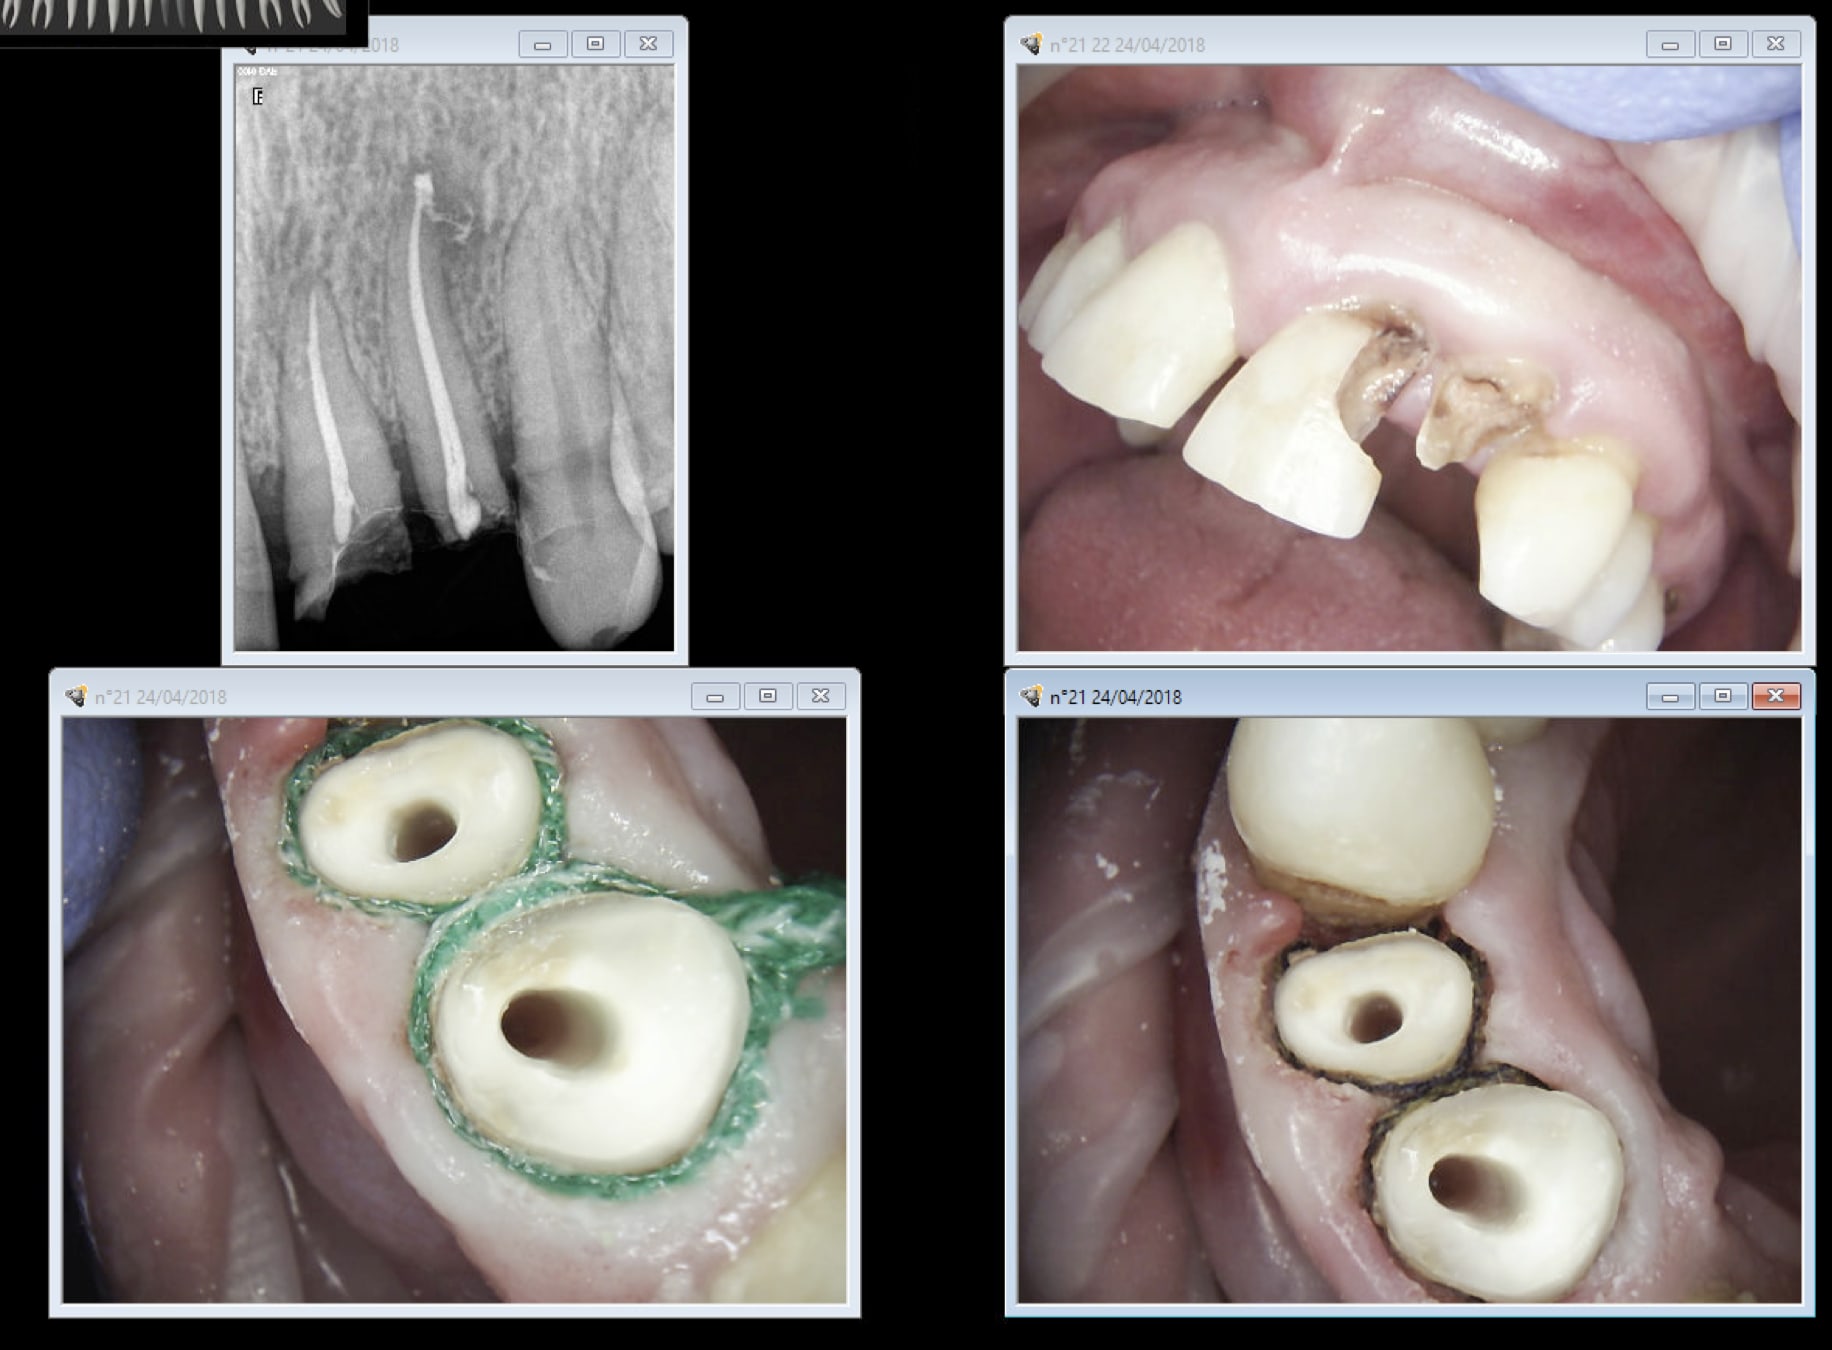

Empreitne dans la foulée. COMME D'HAB.

Capture d écran 2018 04 24 17.02 - Eugenol